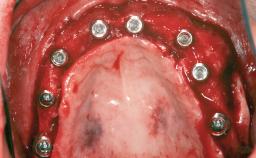

A 47-year-old woman who had suffered from aggressive periodontitis requiring a number of periodontal interventions over more than 10 years was referred by her general dental practitioner and periodontologist for bone augmentation and implant therapy. Her failing dentition had already been scheduled for extraction. The patient expressed a desire for implant-supported fixed restorations and esthetic improvement of her lower face. She had agreed to consult with a maxillofacial surgeon after the referring dentist had suggested bone augmentation. An initial examination by the maxillofacial surgeon revealed mobility of all residual teeth in a patient who was very unhappy with the function of her removable partial dentures. Due to periodontally migrated flaring teeth and loss of occlusal support, the vertical dimension of occlusion was dramatically reduced. The patient was displeased with her lower face because of deepened nasolabial, commissural, and supramental folds.

# of Implants 14

Bone Augmentation Horizontal|Sinus Floor Elevation|Staged|Vertical

Augmentation Materials Autogenous chips|Autogenous block(s)|Xenogenous|Membrane